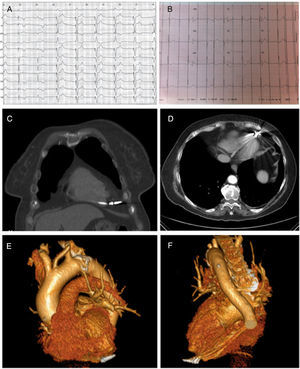

Se presenta el caso de una paciente mujer de 73 años remitida para implante de marcapasos por bloqueo aurículo-ventricular completo paroxístico decidiéndose implante de marcapasos bicameral realizado a través de vena subclavia izquierda con colocación de electrodos de fijación activa en orejuela de AD y en ápex de VD. A las 24h, la paciente refirió dolor torácico en hemitórax izquierdo punzante refractario. Se revisó el dispositivo que mostró fallo de sensado y de captura a máxima energía de estimulación del electrodo ventricular (fig. 1A-B). La radiografía de tórax no mostró alteraciones y la ecocardiografía mostró derrame pericárdico ligero sin signos de taponamiento no pudiendo observar la punta del electrodo. Se realizó tomografía computarizada (TC) torácica urgente que demostró perforación de la pared anterior del VD por el electrodo llegando hasta grasa paracardiaca (figs. 1C-F).

A) Electrocardiograma tras el implante en sala de electrofisiología. B) Electrocardiograma tras la perforación cardiaca. C y D) TC torácica. Electrodo perforando la pared miocárdica penetrando en grasa paracardiaca. E y F) Reconstrucción tridimensional donde se visualiza punta de electrodo traspasando miocardio de pared anterior de VD.